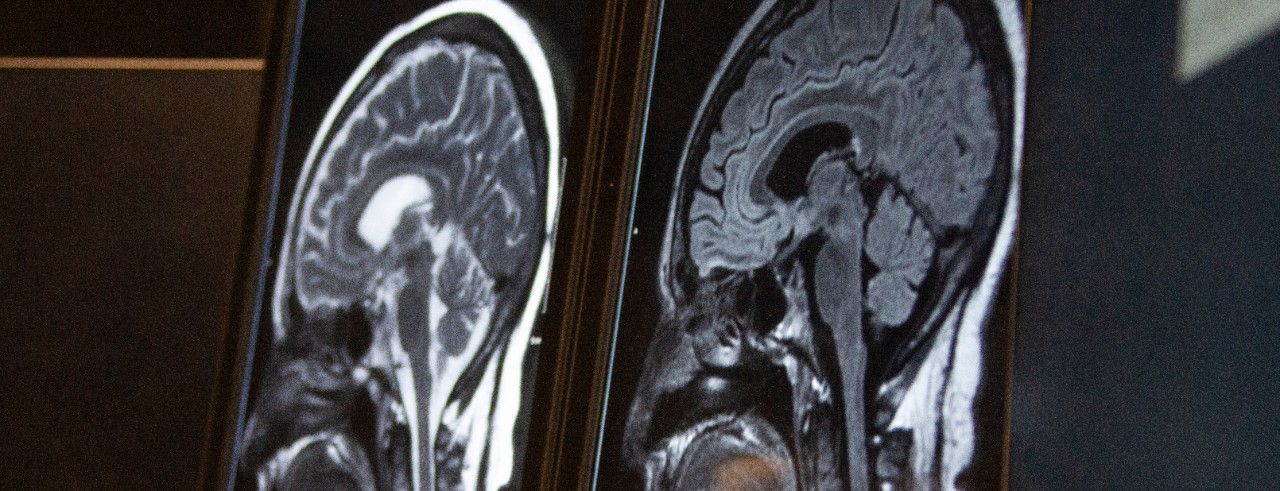

Featured photo at top of brain scans. Photo/Ravenna Rutledge/University of Cincinnati.